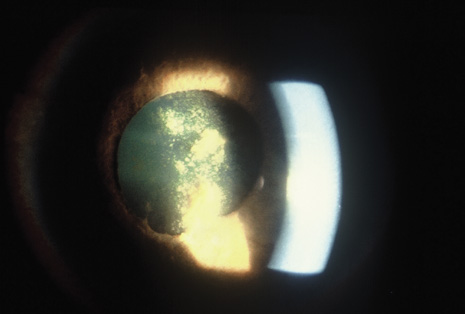

Although keratocentesis had been advocated historically as a treatment for active uveitis, it lost the attention of ophthalmologists until 1919, when Bruckner3 first examined the aqueous humor for diagnostic purposes. Laboratory techniques were revolutionized in the 20th century in areas such as: (a) evaluating very small aliquots of fluid (0.2 to 0.3 mL of aqueous or vitreous), and (b) identifying specific microbial organisms and the predominance of other cell types, antibodies, and proteins in these fluids (Figs. 1, 2, 3, 4, 5, and 6). These advancements have led to the development of diagnostic paracentesis for sight-threatening ocular inflammations that are difficult to diagnose. Witmer4 and O'Connor5 have provided strong evidence that samples of the aqueous humor reflect the antibody-producing capabilities of the iris and ciliary body, particularly when more specific antibody per unit of gamma globulin can be found on the aqueous humor than in the blood of the same patient.6–8 These determinations may be highly significant when one considers the fact that diseased tissue is being bathed in an antibody-containing fluid that is elaborated locally. For instance, in the case shown in Figure 1, the immunofluorescent antibody titer to toxoplasmosis is four times greater in the vitreous aspirate at the time of vitrectomy for repair of retinal detachment than in the plasma. These same considerations have long been recognized in syphilis of the central nervous system, wherein specific antibodies may be present in the cerebrospinal fluid but not in the blood. This is also the case with an unusual presentation of ocular coccidioidomycosis9 or toxocariasis.

Precise identification and culture of bacterial and fungal pathogens from both the aqueous humor and the vitreous fluid can be obtained. Gram's stain and Giemsa's stain smears of centrifuged specimens from the aqueous humor and the vitreous humor frequently demonstrate the bacterial or fungal causative agent. Attempts to isolate bacteria and fungi and to identify them on Gram's stain or Giemsa's stain smears have been most rewarding in the following cases: (a) postoperative endophthalmitis, (b) infection after a penetrating injury of the eye, (c) drug abuse patients with endogenous endophthalmitis (Figs. 21, 22, 23, 24, and 25), (d) patients receiving hyperalimentation, and (4) patients who are immunocompromised as a result of exogenous immunosuppressive agents.